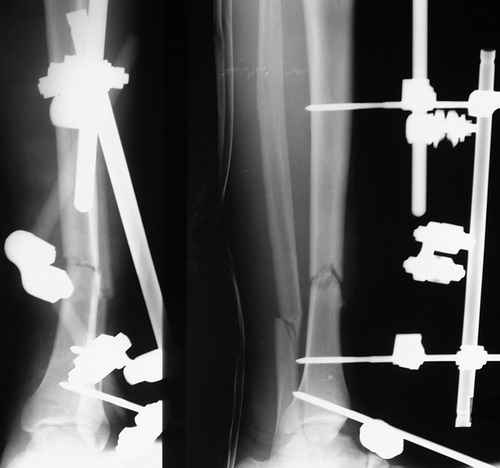

Открытый перелом- пхо+стержневой аппарат-штифтование. Через 4 месяца отек, температура 39….

Удален штифт-резекция+билокальный остеосинтез. Выращивание дистракционного регенерата

Повторное штифтование с рассверливанием. Оставлен дистально «легкий» аппарат для создания компрессии сближенных опилов на 4 недели.